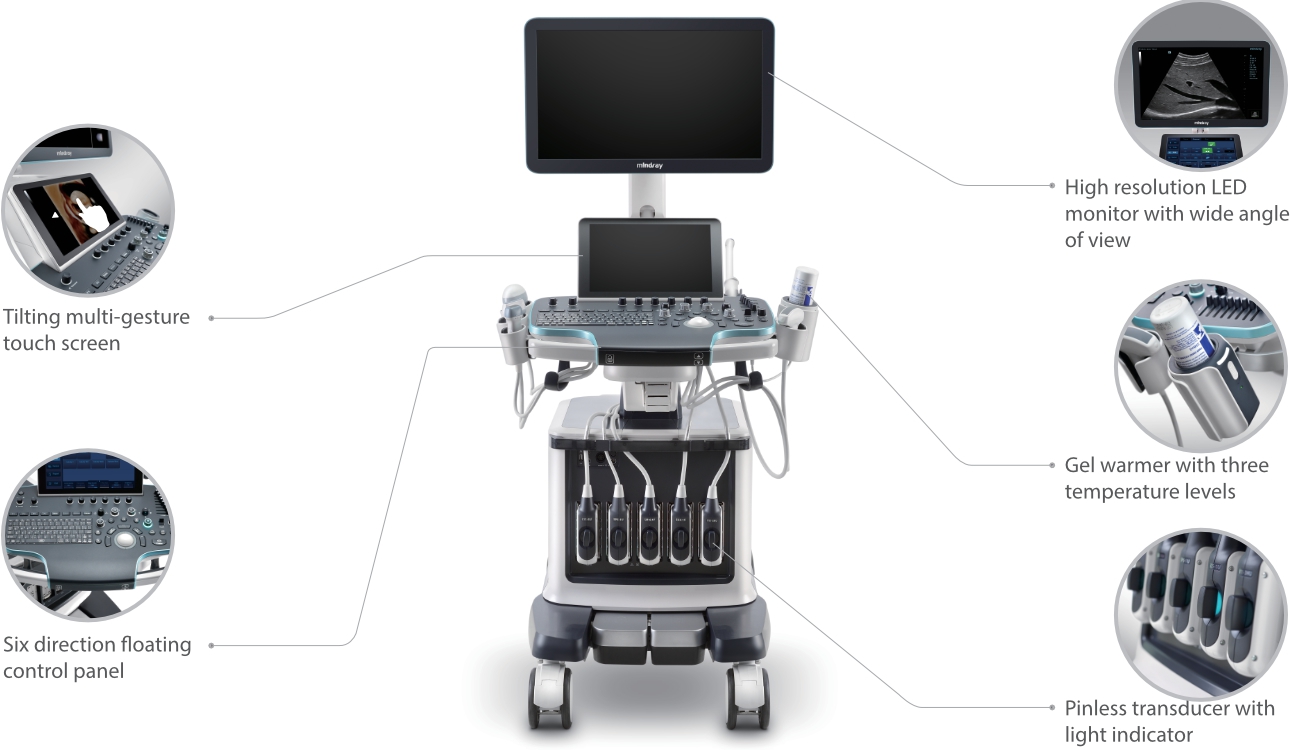

Fin dalla sua fondazione Mindray esplora continuamente nuovi modi per migliorare l'affidabilit├Ā diagnostica. Equipaggiata con la pi├╣ rivoluzionaria tecnologia ZONE Sonography?, la nuova piattaforma ZST+ di Resona 7 porta la qualit├Ā dell'immagine ecografica ad un livello superiore con l'acquisizione per zone e l'elaborazione dei dati canale.

Oltre alla qualit├Ā delle immagini di livello eccellente, Resona 7 migliora anche le capacit├Ā di ricerca clinica il rivoluzionario V Flow per la valutazione emodinamica vascolare, e l'acquisizione piani pi├╣ intelligente dal set di dati 3D per la diagnosi del sistema nervoso centrale fetale. Combinando il pi├╣ intuitivo funzionamento multi-touch basato su gesti e tutte le caratteristiche cliniche essenziali, Resona 7 sta veramente portando nuove tendenze nellŌĆÖinnovazione dellŌĆÖecografia.